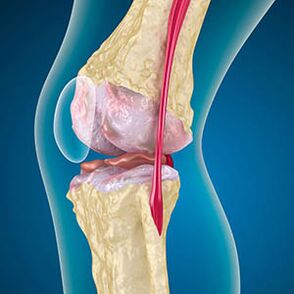

Avec l'arthrose, le cartilage qui couvre les bords des os est l'abrasion ou complètement absent. Le tissu endommagé n'est pas une source de douleur, car il n'a pas de receveurs. L'inflammation dans les structures voisines provoque des symptômes caractéristiques.

Le corps continue la régénération des tissus endommagés, mais le cartilage se développe inégalement. En conséquence, les irrégularités qui endommagent d'autres éléments de l'articulation sont formées. La nature des ostéophytes s'explique par la compensation du cartilage des articulations lisses. Une autre version indique que la croissance des "éperons"Il est associé à une tentative de stabilisation de l'articulation médiale ou latérale en raison d'un affaiblissement musculaire.

Dans la première étape de l'arthrose, qui est détecté par accident, il y a une légère augmentation des éperons osseux. La croissance apparaît dans les lieux de l'instabilité d'articulation la plus élevée. En général, les patients éprouvent rarement de la douleur ou de l'inconfort pendant le mouvement.